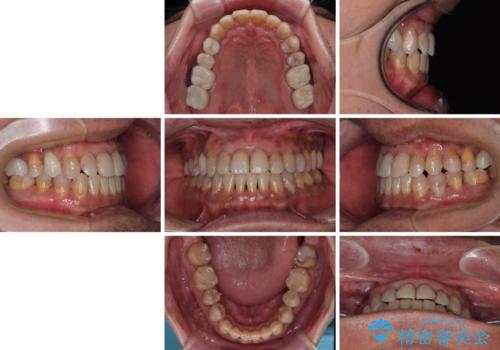

- 前歯のクロスバイトを気にして来院された患者様です。

40代男性で、インプラント補綴治療も経験されている方で、矯正治療をしても良いのかと悩んでいらっしゃいました。

下顎骨の左右のずれがあり、下顎全体が前方に出ている状態であったので、無理をせずにワイヤー装置にて矯正治療を行うこととしました。

クロスバイト改善には難儀しましたが、咬みやすく、笑ったときに清潔感ある口元に仕上げることができました。